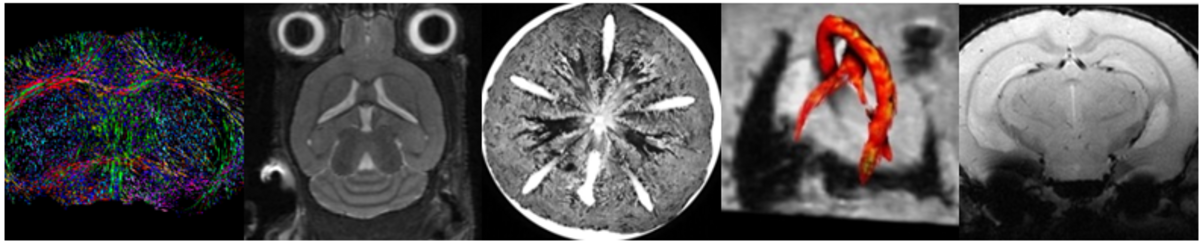

Small Animal MRI Symposium 2018 in Münster

Termin vom 07.06.2018 - 08.06.2018

Join usfor the 1st Small Animal MRI Symposium in Münster.FlyerWebsite